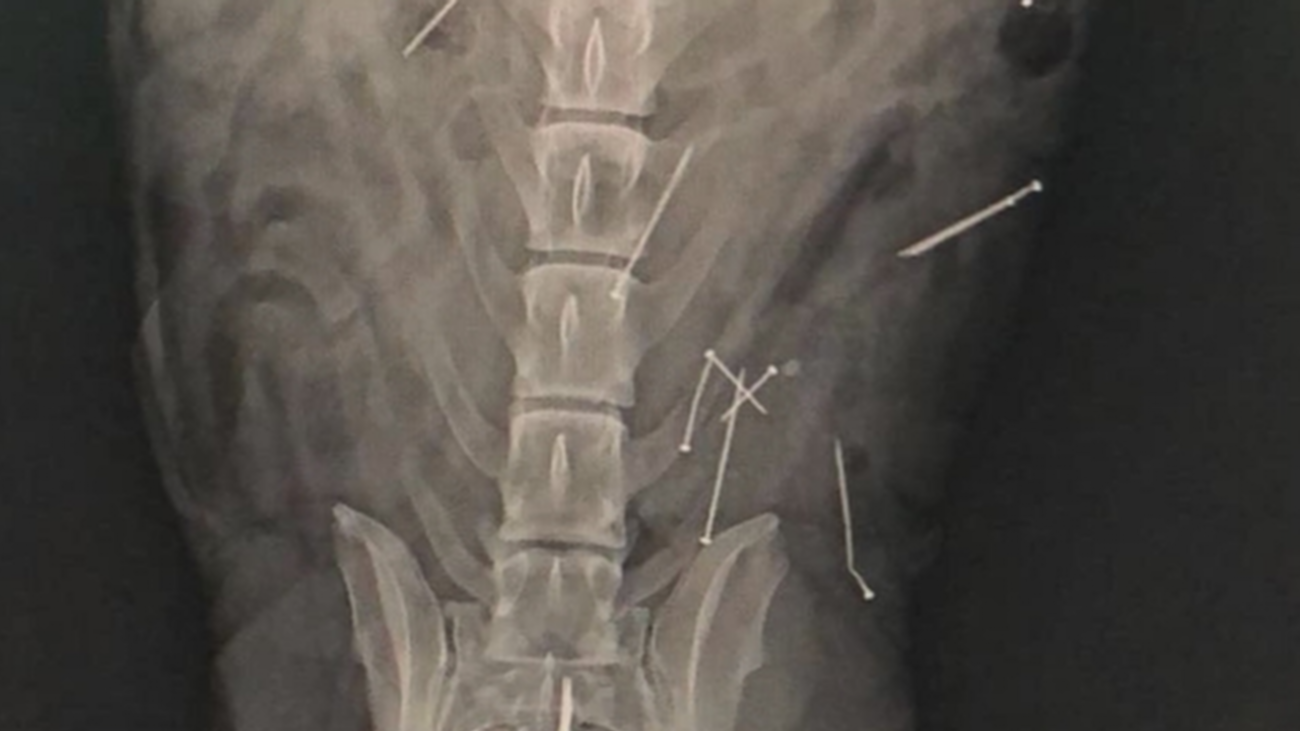

En Brunete los veterinarios están en alerta: alguien está repartiendo salchichas con clavos por los parques del municipio y ya han dos canes afectados por su ingesta.